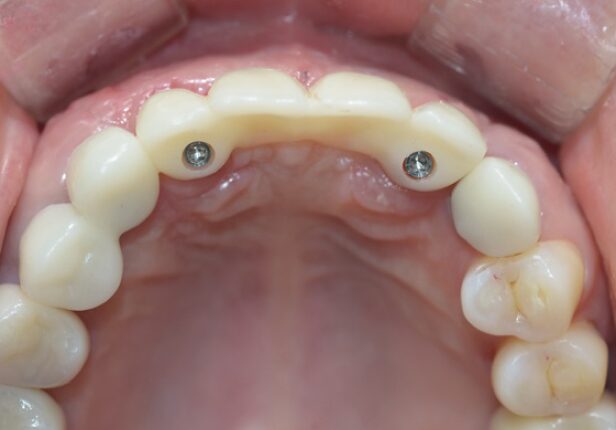

Coroa Final

caso de estudo